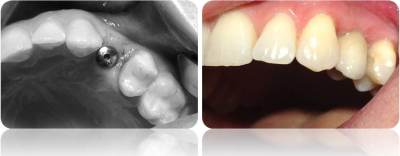

Gallery

Galeria